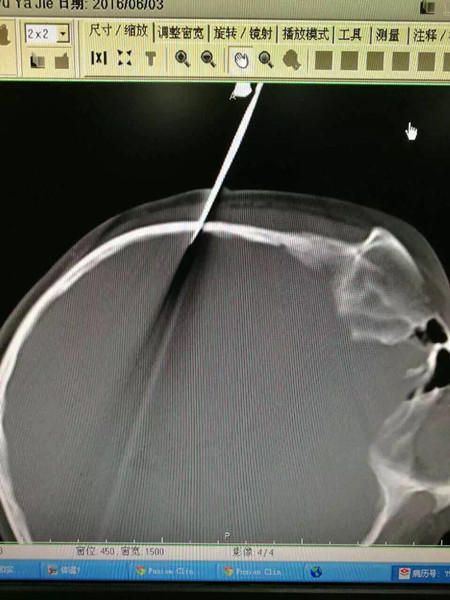

gif_animation 中国・上海の病院に、1人の女の子が運ばれてきた。女の子の頭には、ハサミが深く突き刺さっていた。彼女の父親は、”教育” のため、ハサミでこの10歳の娘を脅そうとしたという。しかし結果的に、ハサミは深く娘の頭に突き刺さる事となった。5枚。